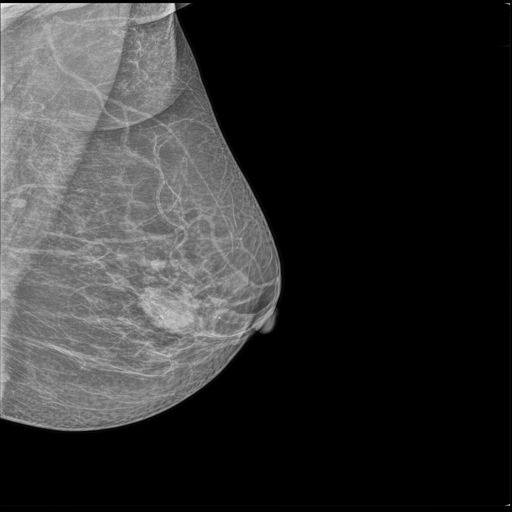

MammoAI revolutionizes breast cancer diagnostics by transforming mammograms into clear, evidence-based reports with actionable next steps. The app addresses critical delays in analysis and limited specialist access, providing faster, clinically informed insights directly from medical imaging and literature.

- Mammogram Upload & Preprocessing – Users can upload images in common medical formats; the app prepares the image for analysis.

- Annotation + Notes – Health specialists can optionally mark areas of interest and add notes to guide the analysis.

- Intelligent Diagnosis & Treatment Reports – Fine-tuned models and LLM-powered agents analyze images and notes, querying specialized medical knowledge bases to generate actionable insights.

- Comprehensive Final Report – Combines mammogram findings, diagnosis, recommended next steps, and practitioner notes into a single, clear report.

Use the following publicly available mammogram images for testing purposes: